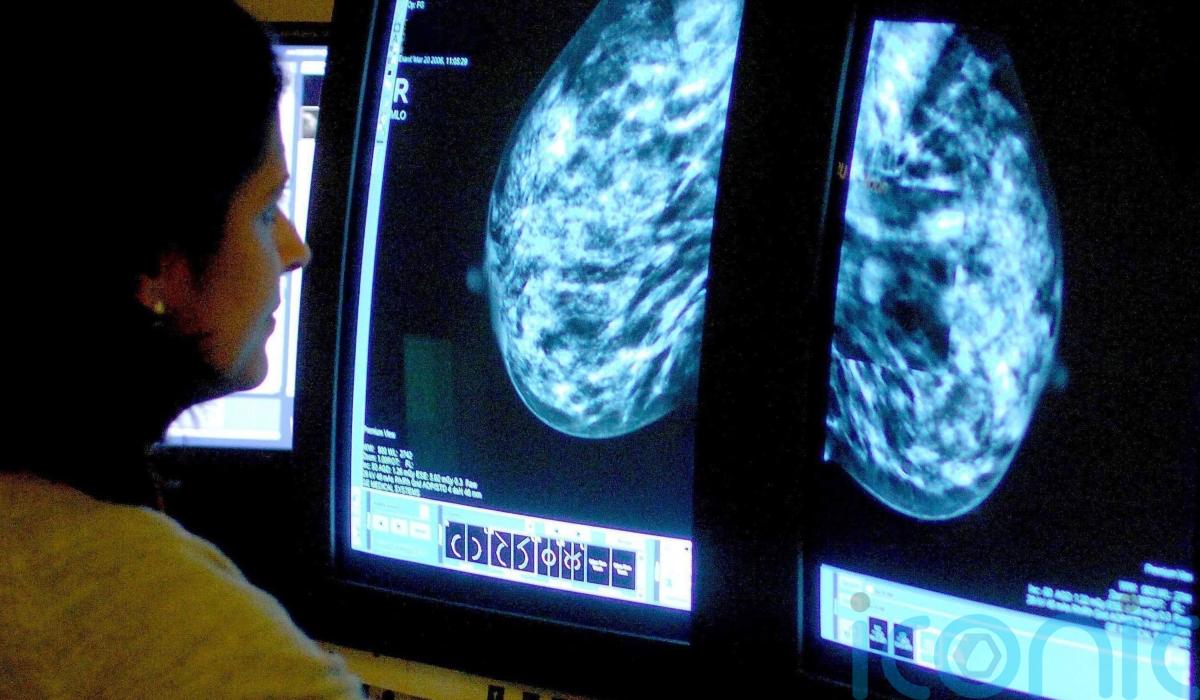

The importance of red flag referrals and screening routes for early diagnosis of cancer to improve survival rates for people in Northern Ireland has been highlighted in a report.

The study from the Northern Ireland Cancer Registry (NICR) at Queen’s University Belfast used research conducted on patients diagnosed between 2018 to 2020.

The Routes to Diagnosis report shows a strong relationship between a patient’s route to diagnosis and how advanced their cancer was at diagnosis.

The report found higher proportions of patients diagnosed with early-stage disease came through screening or red flag referral routes, with a higher proportion with advanced (late-stage) disease coming from emergency presentation.

The data showed that one-year survival was 87% for those diagnosed via red flag referral compared with 42% for those diagnosed following emergency presentation, and more than 98% of those diagnosed via screening are alive one year after diagnosis.

It also found that the two years from diagnosis to survival ranged from 33% for those diagnosed via an emergency presentation route to 80% for those diagnosed through a red flag referral route.